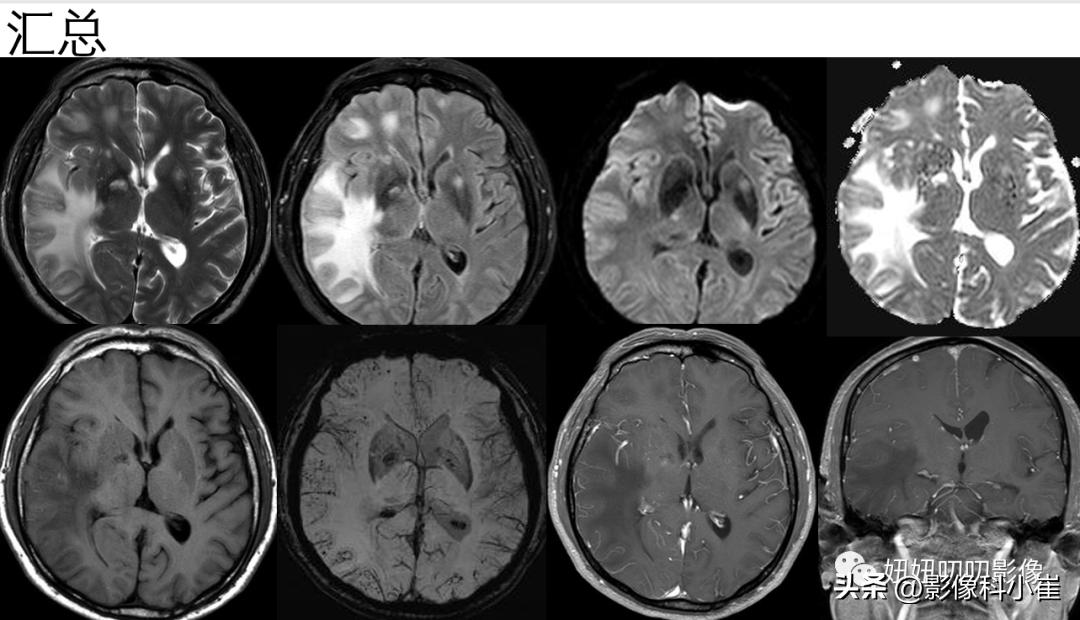

①:看到SWI能想到,脑淀粉样血管病,出院诊断也是这个;

③:原理:Aβ蛋白的清除减少,Aβ蛋白沉积于大脑皮质及软脑膜等处的微小血管,外膜增厚,血管缺血改变,然后又分泌炎性因子,破坏内中膜血管壁,导致出血。

④:影像:脑叶出血+脑微出血+大脑凸面蛛网膜下腔出血+铁沉积——提示 脑淀粉样血管病;临床:阿尔兹海默病+年龄。